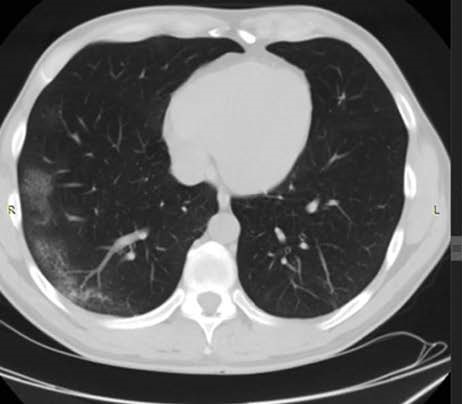

• the computed tomography system 64-slice manufactured by NIPK Electron Co. for primary assessment and differential diagnostics of chest diseases, as well as for revealing concomitant diseases. The modular CT unit can be equipped with a computed tomography system with another slice number as an option. According to the interim methodological guidelines “Prevention, Diagnostics, and Treatment of a new Coronavirus Infection” developed by the Ministry of Health of Russia, a CT scan is considered one of the basic methods of COVID-19 diagnosis.

The computed tomography system 64-slice (CT) installed in the module unit is equipped with a wide set of specialized software applications for diagnostic imaging in patients with respiratory disorders, vascular abnormalities, cancer, as well as for assessment of cerebral, renal, and hepatic blood supply. Thanks to this, CT is in high demand not only during the COVID-19 pandemic.